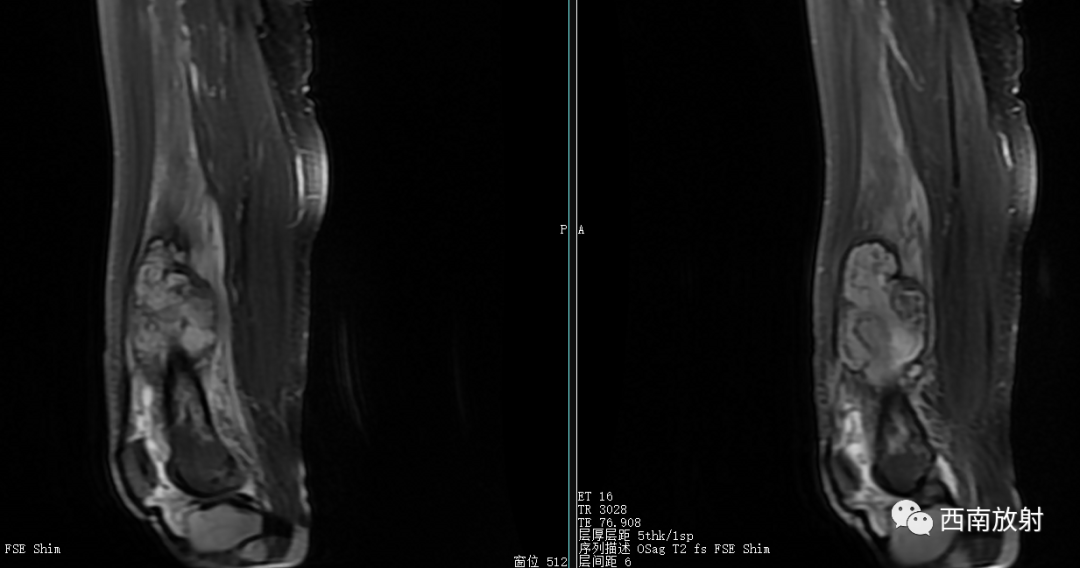

现病史:患者于2021年8月17日开始出现右膝关节疼痛,无畏寒发热、恶心呕吐、咳嗽咳痰,无破溃、流脓,于8月20日在我院急诊科就诊,考虑关节炎,予口服双氯芬酸钠缓释片及泼尼松等药物治疗,无好转,随后转到天等县中医院就诊,予行右膝关节抽液及外敷中成药治疗(具体不详),4天前开始出现解黑便,每日1次,每次量约200g,伴有头晕、乏力,无腹痛、呕血、昏迷及呼吸困难等。今来院就诊,在门诊发现血压偏低,85/56mmHg,右膝关节抽出45ml的红色积液,右膝关节MRI示有骨髓炎,生命征不稳定,有转入我科指征,我科会诊后转入治疗。患者病后精神、睡眠差,未进食,大便如上述,小便色黄,量尚可,体重无明显变化。

大体病理:右大腿中下段内侧骨膜外见一腔隙,约3X3X4cm,内有较多血凝块,有少许脓液,股骨下段周围有少许脓液,少量疤痕形成,右膝关节内有少许脓液,见有少许脓苔,右骨髓腔未见破坏,骨髓腔内有少许脓液,已被疤痕织包裹。

诊断:慢性骨髓炎,周围软组织脓肿。

CT显示骨破坏、脓肿、死骨及骨膜增生、骨质增生硬化,呈骨小梁密度增高、模糊,髓腔密度增大、狭窄,皮质增厚。MRI显示早期骨髓内广泛分布的斑片异常信号,与邻近正常骨髓信号相比较,T1WI信号减低,T2WI信号增高,脂肪抑制T2WI 或STIR 等序列上病变显示更清楚,骨皮质周围软组织内呈弥漫分布的T1WI低信号及T2WI高信号影,边界模糊。出现骨膜反应,骨皮质不规则破坏,脓肿及死骨形成。

关于脂肪征

▲MRI脂肪征:病灶内单发或多发,T1WI上呈高信号,脂肪抑制序列信号明显减低。急性骨髓炎的脂肪球征发生机制:骨髓炎的炎性反应致骨髓腔内充血、渗出及水肿最终导致髓内压力增高,髓腔内大量脂肪细胞(即髓脂细胞)快速坏死释放出游离脂质并聚集形成脂肪球[2-3]。